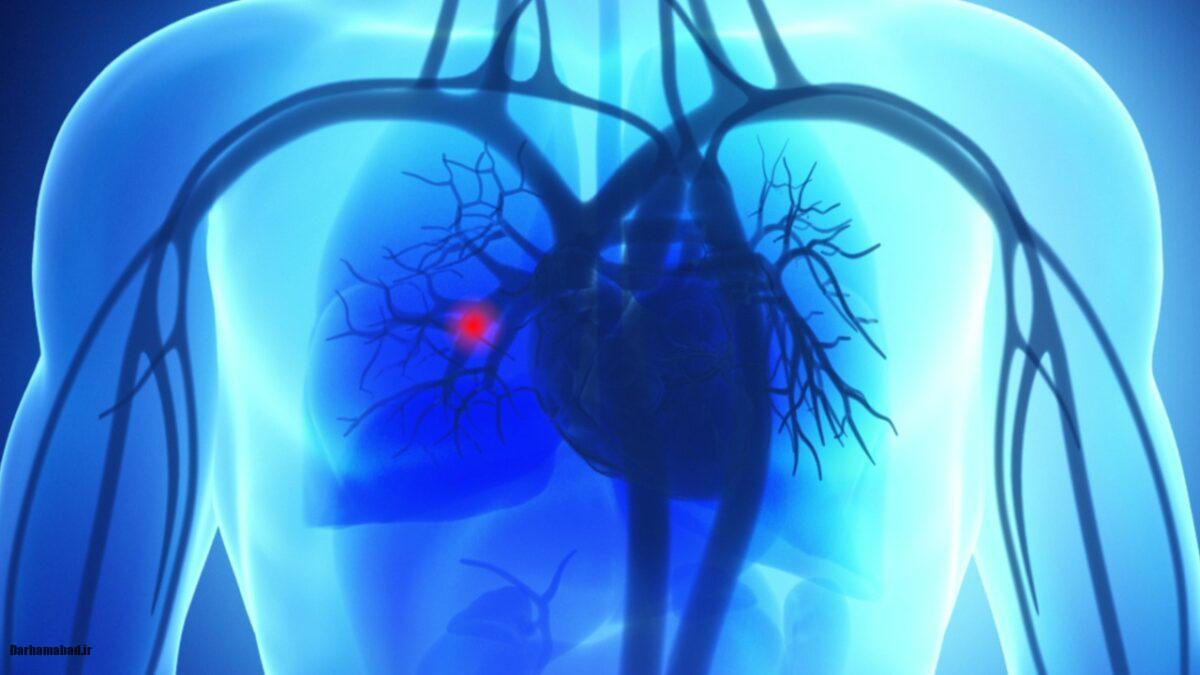

در پاسخ آمبولی ریه چیست؟ باید بگوییم که، آمبولی ریه یکی از شرایط پزشکی جدی است که در آن یک لخته خون (ترومبوز) یا هر مادهی خارجی دیگر وارد ریهها میشود و مانع از جریان خون طبیعی در ریهها میشود. این مشکل میتواند به سرعت به یک وضعیت تهدیدکنندهی زندگی تبدیل شود و بنابراین شناسایی علائم آن در مراحل اولیه، نقش حیاتی در بهبود وضعیت بیمار دارد. در این مقاله، قصد داریم به بررسی علائم آمبولی ریه، عوامل خطر، روشهای تشخیص و درمانهای موجود بپردازیم.

آمبولی ریه زمانی رخ میدهد که یک لخته خون از قسمتی دیگر از بدن (معمولاً از پاها یا لگن) به ریهها منتقل میشود و مانع از جریان خون در ریهها میشود. این اتفاق میتواند به اختلالات شدید تنفسی، نارسایی قلبی و در مواردی حتی مرگ منجر شود.